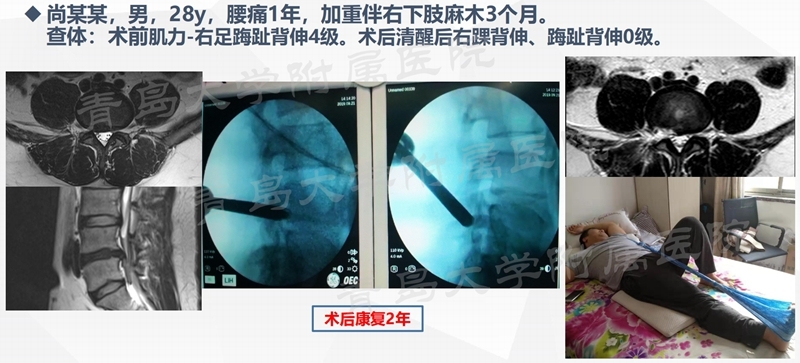

典型案例

案例一